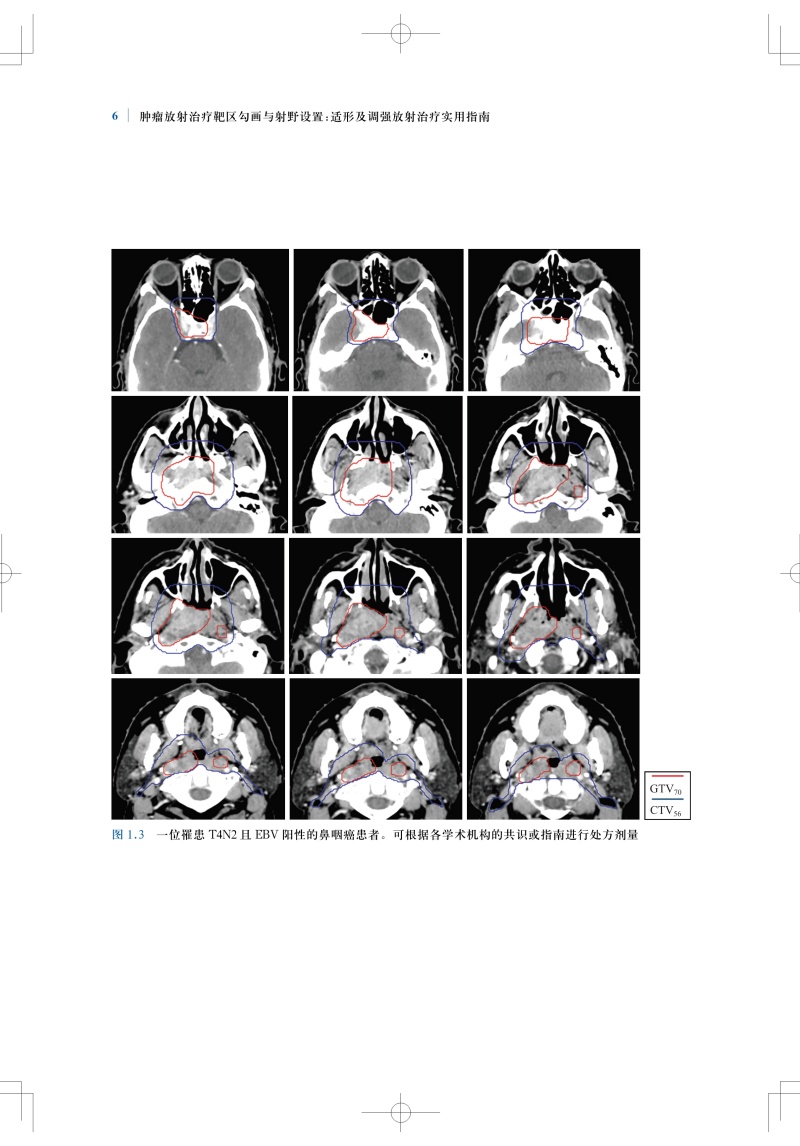

肿瘤放射治疗靶区勾画与射野设置是疗效的基石,精准的靶区范围的确定和勾画可确保肿瘤患者的放疗效果。全书结合大量影像图片,按章分别详细介绍了各种常见病变的具有临床依据的精确的CTV勾画和指南,包括鼻咽癌、甲状腺癌、早期乳腺癌、肺癌、直肠癌、前列腺腺癌、膀胱癌等;并对相关的淋巴引流区解剖进行了勾画,且逐层显示并说明注意事项。本书内容实用,可为放疗医师对常见肿瘤进行适形放疗和调强放疗时的靶区勾画及放射野设置提供指导和参考。